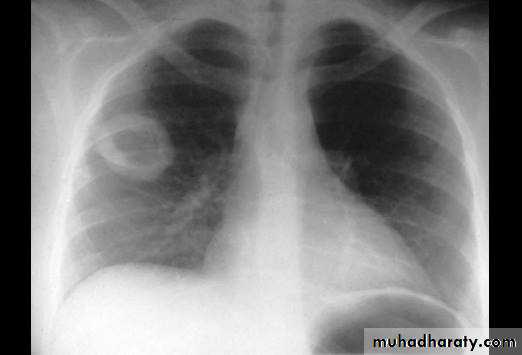

Causes(pneumonia ,pulmonary infarction & pulmonary contusion )Cavity

1/contain air only1)Thin walled-central =pneumatocele

-peripheral = Emphysematous bullae

2)Thick walled-regular= chronic abscess

-irregular =Tumor with central necrosis

2/contain air +fluids :acute abscess

ruptured Hydatid cyst

3/air +nodule :mycetoma( fungus in previous cavity)

Cavity ( air containing lesion )

Thin walled <3mm

Thick walled >3mm

Cavity with air fluid level

Air fluid level with membrane (ruptured hydatid cyst )